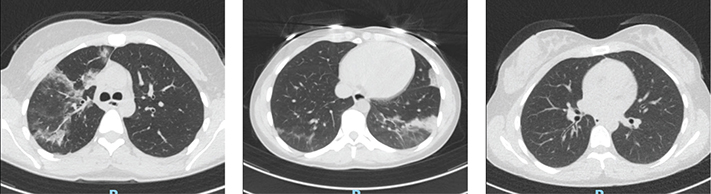

Case 1 was a 25-year-old female with mixed connective tissue disease (MCTD). She was treated with rituximab every 6th month and prednisolone 5 mg daily. The patient had received three doses of the SARS-CoV-2 mRNA vaccine but had not responded serologically. In February 2022, she developed a fever and cough and tested positive for SARS-CoV-2 by PCR. She experienced a short clinical improvement after 14 days of symptoms, but after a couple of days, the symptoms returned. After 8 weeks of persistent symptoms with fluctuating fever, cough, and dyspnea, she was assessed at the Infectious Disease Clinic. The PCR for SARS-CoV-2 was positive in the nasopharynx but negative in blood. SARS-CoV-2 serology was negative. C-reactive protein (CRP) was 30 mg/L (normal range <5 mg/L). She did not require supplemental oxygen. A chest computed tomographic (CT) scan revealed an image consistent with atypical pneumonia, and because the nasopharyngeal culture was positive for Haemophilus influenzae, she was treated with doxycycline against suspected pneumonia. No treatment against SARS-CoV-2 was prescribed. She experienced 1 week of symptomatic improvement, but then the fluctuating fever, cough, and dyspnea returned and persisted. During the following 4 months, she was reassessed several times at the Infectious Disease Clinic (May, June, July, and August), and every time she tested negative by PCR for SARS-CoV-2 in the nasopharynx. CRP was approximately 30 mg/L. During the first three assessments, the nasopharyngeal culture was positive for Haemophilus influenzae, resulting in antibiotic treatment on every occasion (doxycycline, amoxicillin, and co-trimoxazole) with no symptomatic improvement. Immunoglobulins in serum were tested with a normal IgG at 8.0 (normal range 6.7–14.5), a low IgM at 0.15 (normal range 0.27–2.1), and a low IgA at <0.05 (normal range 0.88–4.5). As she had not had any problems with infections earlier, she had no history of immunoglobulin treatment. A new chest CT in June showed ground-glass opacities and multilobar consolidation. This image was consistent with a pattern of organizing pneumonia (OP) (Figure 5a), which gave rise to interdisciplinary discussions on whether this was an infectious condition or an interstitial lung disease associated with her MCTD (MCTD-ILD). The patient was planned for a follow-up CT scan after 6–8 weeks. In August, she was again assessed at the Infectious Disease Clinic because of persistent symptoms of high fever, effort dyspnea, cough, and fatigue. CRP was now 62 mg/L, and a new chest CT scan revealed progress of OP (Figure 5b). She was admitted to the hospital and underwent a bronchoalveolar lavage (BAL) that surprisingly showed a positive PCR for SARS-CoV-2. The cycle threshold (Ct) value was 31.3, and the strain was typed to BA.2 (the predominant variant in February 2022), strongly suggesting persistent SARS-CoV-2 infection rather than reinfection. The PCR in the nasopharynx remained negative. The patient was treated with nirmatrelvir/ritonavir (Paxlovid) for 10 days and a double dose (300 + 300 mg) of tixagevimab-cilgavimab (Evusheld). After 5 days of treatment, CRP was normal (Figure 1), and the patient felt relief from the clinical symptoms. After that, she gradually recovered fully. A follow-up CT scan was performed 2 months later, showing regression of earlier pulmonary infiltrates (Figure 5c), and the patient self-reported resolution of all symptoms. This recovery remained on the latest follow-up, 5 months after discharge.

Figure 5

Figure 5. CT scans of Case 1 in (a) June, (b) August, and (c) October, demonstrating a pattern interpreted as organizing pneumonia that initially progressed and then regressed after antiviral treatment.